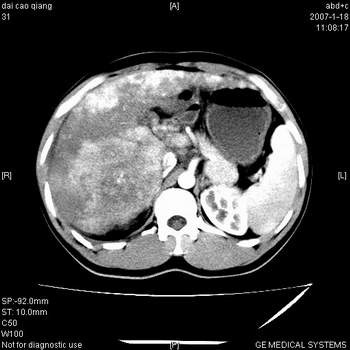

符合巨块型肝癌表现:

1、平扫低密度,增强后表现为快进快出。

2、动脉期可见迂曲的动脉供血血管

3、并可见门静脉右支癌栓形成

4、可见假包膜

5、腹主动脉旁结节影,考虑肿大淋巴结。

典型的肝右叶巨块型肝癌破裂、门脉瘤栓形成。

肝右叶巨大不均匀低密度肿块,前缘有假包膜,增强明显的呈快进快出表现,门脉右支有癌栓,病人虽然年轻但还是首先考虑肝右叶巨块形肝癌,病人血象高只能说有合并感染。不支持肝脓肿。

巨块型肝癌并门静脉右支癌栓